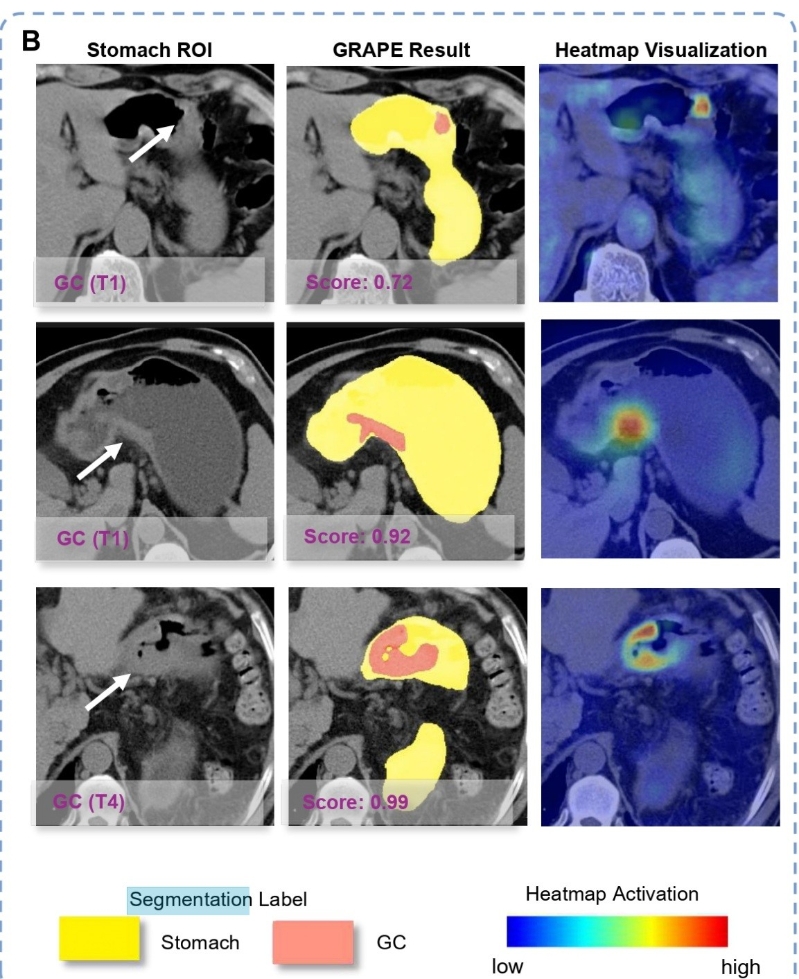

胃癌AI篩查模型(中間黃色縱軸)可提前發現胃癌 未來將助力多癌篩查 患者只需付正常CT費用 “平掃CT+AI是一個在內鏡之前初篩的手段,通過平掃CT這一非常舒服、無創、便宜的檢查方式,運用AI給病人的風險分級。如果AI算法認為是胃癌高風險,患者可以再去做一個內鏡,這樣,患者的依從性會更高,篩查普及率也會更高。” 專家認為,這一模型廣泛應用後,早期胃癌病人被發現的比例會明顯提升,“哪怕每年提升5%-10%,貢獻都是非常大的。” 據介紹,目前,該項目率先在浙江、安徽等地開展大規模人群篩查,有需要的患者可以在浙江省腫瘤醫院、浙江麗水人民醫院、寧波大學附屬人民醫院等咨詢。費用方面,患者只需要繳納正常CT的費用就可以。 “胃癌的AI篩查印證了我們這套技術方案可以在消化道腫瘤的治療方面得到更廣泛的應用,未來,希望平掃CT+AI可以應用在更多的多癌篩查上,用一次平掃篩查所有的腫瘤,產生更大的社會價值和醫學臨床價值。這一定是革命性的一幕,也會整個改變現在癌症的診療流程。作為AI的科學家,我們希望把不可能變成可能。” 夏英達說。(完) 【編輯:馮赫棠】